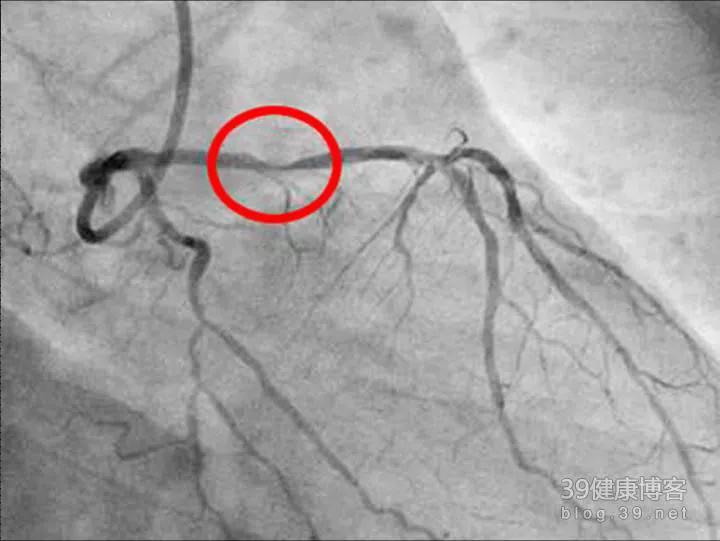

出现了胸痛,我们可以进行心电图检查,查心肌损伤酶谱,来了解心脏有无缺血损害,但这并不能了解冠脉病变的严重程度,若要明确是否存在冠心病,当前主要依靠冠脉造影进行检查。冠脉造影是诊断冠心病的金标准,它可清晰显示冠脉狭窄以及冠脉的狭窄程度,但并非冠脉造影一发现血管狭窄,就能诊断为冠心病,这时主要看血管的狭窄程度:如果冠脉狭窄程度达到50%,那么此时已经达到冠心病的这段标准。因此,如果冠脉狭窄只有40%,那么此时是不能诊断为冠心病的。